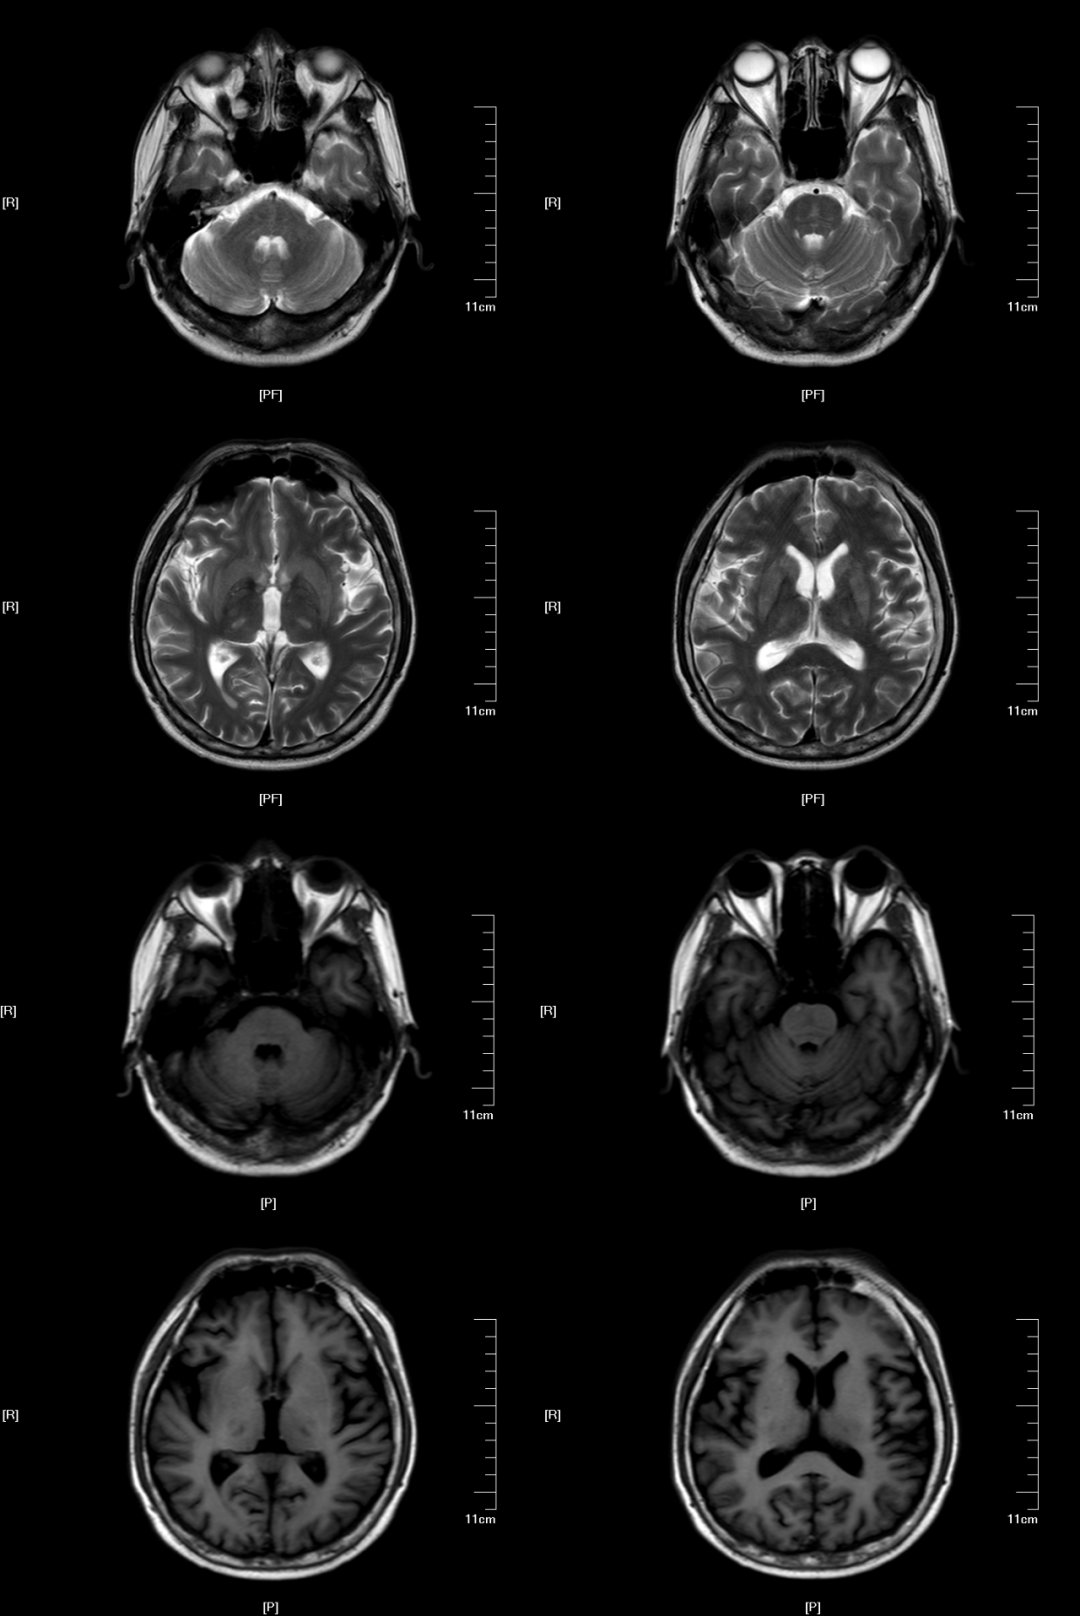

(2)CPM,病灶多位于桥脑基底部而桥脑腹侧不受累,病灶形状多种多样,可为条片状(位于中脑基底部中线,如本例)、斑片状、圆形或卵圆状、「三叉戟」或「猪鼻」样,T1WI 呈低信号,T2WI 及 FLAIR 呈高信号,病灶边界清晰,部分患者出现 DWI 高信号,有利于疾病的早期发现,出现强化提示血脑屏障破坏。

“三叉戟”样病灶,桥脑腹侧及被盖未受累

“猪鼻”样病灶,桥脑腹侧及被盖未受累,中脑被盖束未受累(蓝箭头)

圆形病灶,位于桥脑基底部,桥脑腹侧及被盖未受累